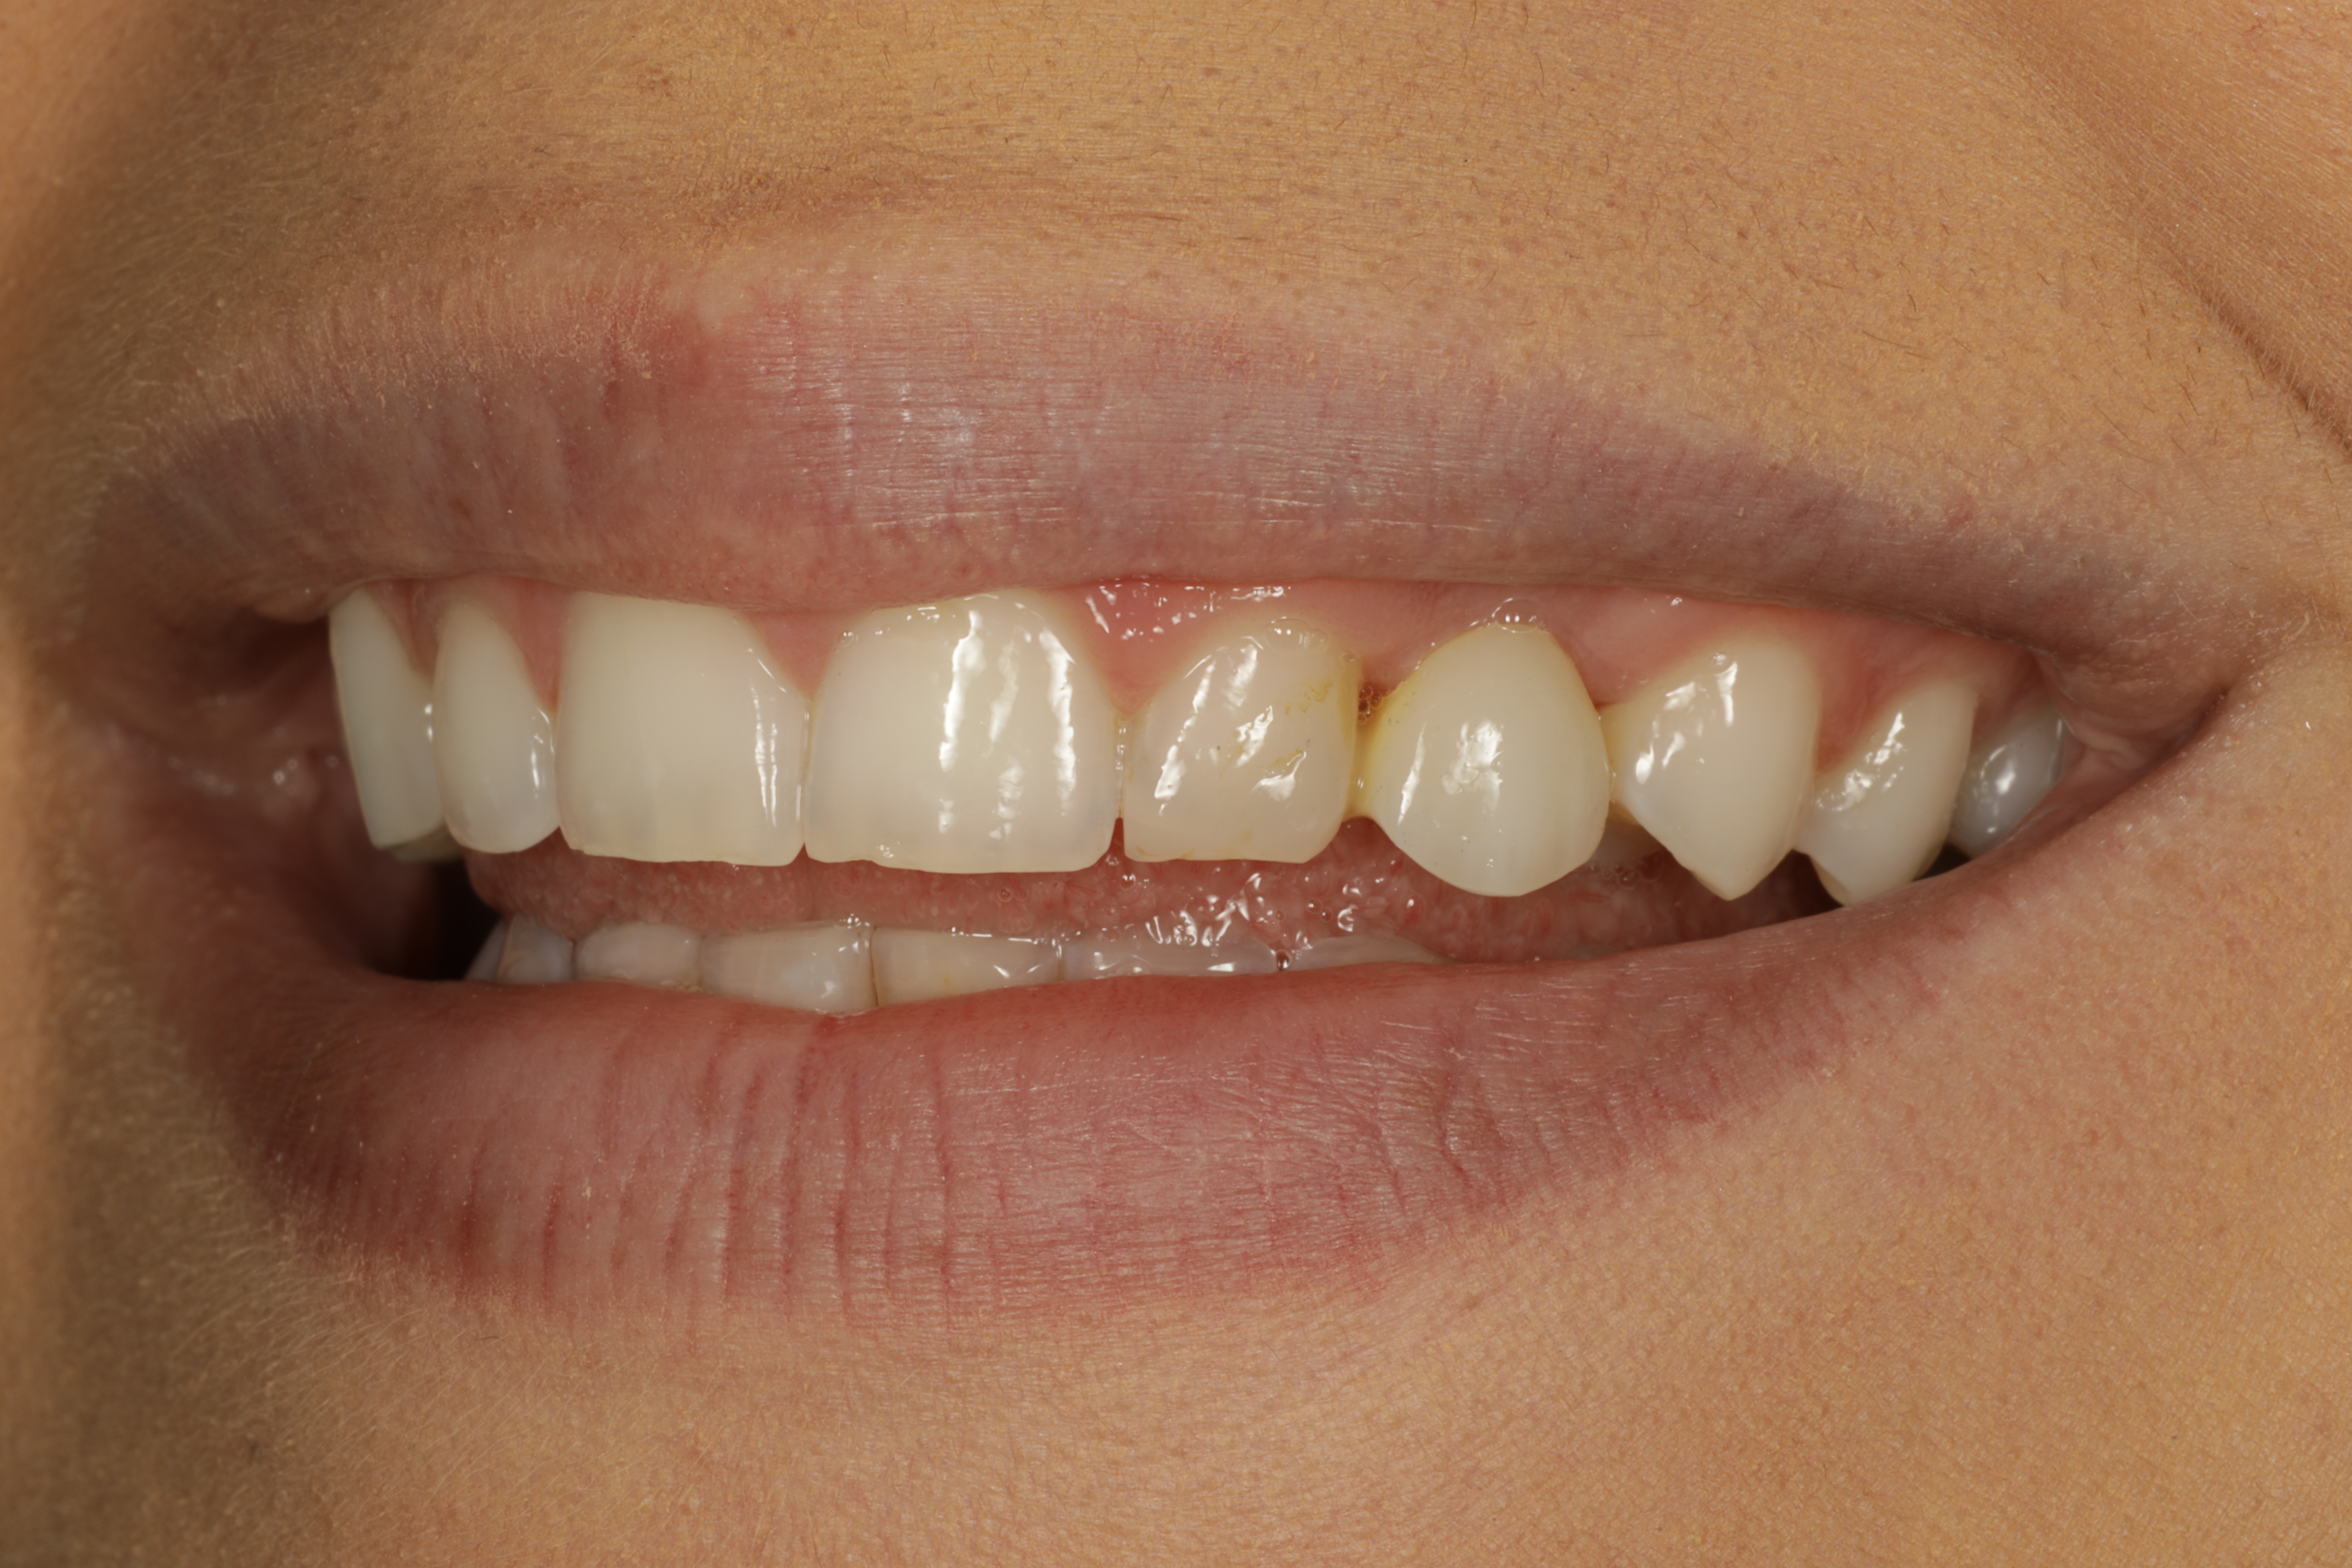

Alkutilanne läheltä

Lopputilanne läheltä